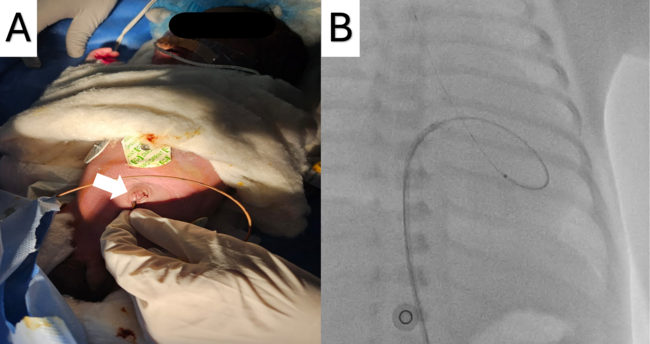

After obtaining informed consent from the parents, the neonate was planned for balloon aortic valvuloplasty (BAV) via the umbilical vein, which had been preserved by inserting a small 4F catheter (Figure A). A 0.014-inch regular workhorse percutaneous transluminal coronary angioplasty (PTCA) wire was inserted and advanced via the umbilical vein through the ductus venosus into the inferior vena cava to the right atrium (RA) (Video 1). Because of a lack of wire support, further advancement was not possible without catheter assistance. A 4F catheter was upgraded to a 5F sheath and a 5F right coronary artery catheter was advanced until it reached the RA. The wire was then manipulated and advanced into the left atrium and subsequently into the left ventricle (LV) through the patent foramen ovale (Video 2). An attempt to cross the aortic valve (AV) with the wire failed because of inadequate support. A Renegrade microcatheter (Boston Scientific) was introduced into the LV (Figure B); the AV was successfully crossed and the PTCA wire was parked in the descending aorta (Video 3). Following microcatheter removal, BAV was performed traditionally with a 4 x12-mm coronary angioplasty balloon, as the annulus measured approximately 6 mm. The post-procedural echocardiographic peak gradient was 18 mm Hg, and the procedure time lasted approximately 1 hour. The plan was to do a repeat BAV from the femoral route 1 month post-procedure.